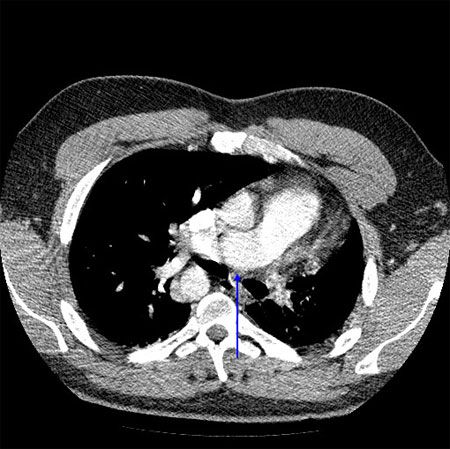

An ECG showed no significant abnormalities. A prominent right pulmonary artery, a right-sided aortic arch, cardiomegaly, and diminished left lung volumes were seen on a chest radiograph (Figure 1). An echocardiogram demonstrated normal chambers with no systolic dysfunction, no evidence of valvular or congenital heart disease, and normal pulmonary artery pressures. CT angiograms (CTAs) of the chest (Figures 2 and 3), a cardiac MRI scan (Figure 4), and a ventilation-perfusion (V/Q) lung scan (Figure 5) were also obtained. Pulmonary function tests (PFTs) revealed a moderate restrictive pattern (total lung capacity, 68% of predicted) with a mildly decreased carbon monoxide-diffusing capacity (76% of predicted) as per the ATS/ ERS task force (2005) standardization guidelines.

The CTAs showed complete absence of the left pulmonary artery, an enlarged right pulmonary artery, and a hypoplastic left lung (Figures 2 and 3). Isolated complete absence of the left pulmonary artery, an enlarged right pulmonary artery, a hypoplastic left lung, and a right-sided aorta were seen on the cardiac MRI scan (Figure 4). The V/Q lung scan showed hypoventilation of the left lung, with complete absence of left lung perfusion (Figure 5). These findings confirmed the diagnosis of isolated unilateral absence of pulmonary artery (UAPA).